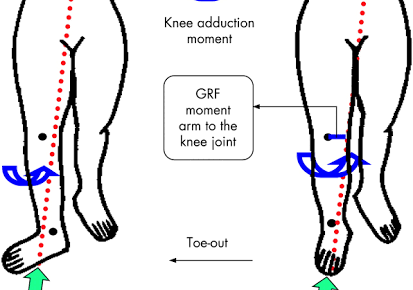

こんにちは!横浜本牧パーソナルトレーナー宮原崇です。 今日から8月ということで、個人的に1年のうちで一番好きな月なので、朝からワクワクしております。 さて、昨日の続きです。 ひざ痛の多くの方が足裏の感覚情報が低下して、そ…

こんにちは!横浜本牧パーソナルトレーナー宮原崇です。 今日は夏晴れでセミの鳴き声も心地よいです。 さて、午前のトレーニングセッションを終えてこれから午後の部となりますが、ひざ痛の方の多くが持っている身体の特徴をお伝えいた…